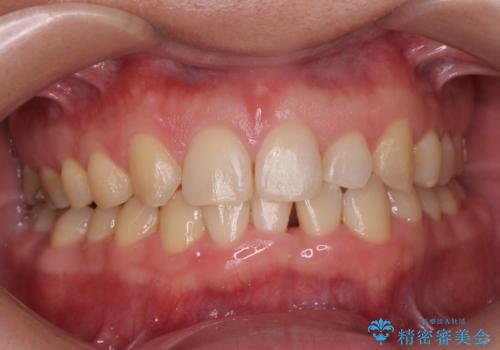

前歯のすき間 歯のがたつき

- 前歯のすき間とがたつきを主訴に来院。

右上の前歯は過去にがたつきがあったとのことで抜いてしまっていました。

歯の数を合わせるために、下の歯を1本抜いて矯正しています。

下の前歯を抜歯したことでブラックトライアングルができましたが、仕上げにIPRを加えることで目立たなくすることができました。